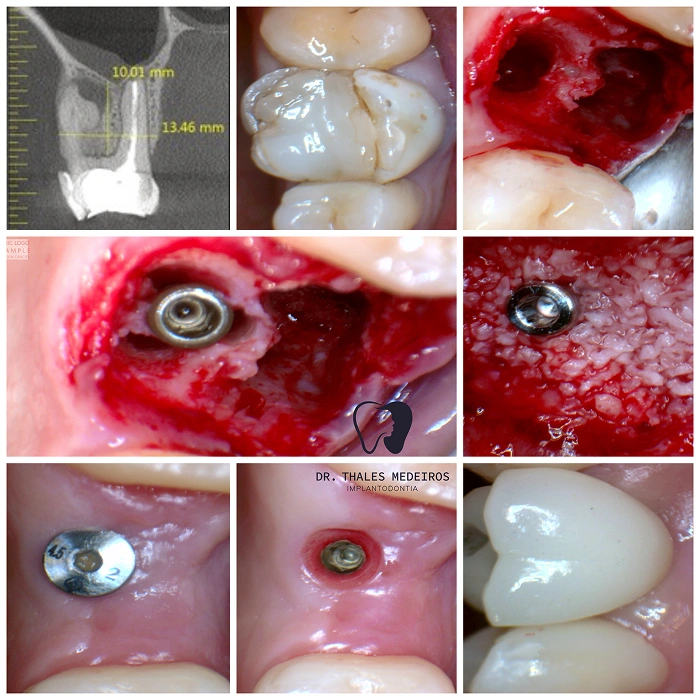

Implantes Dentários: Sorrisos restaurados com segurança e precisão

Recupere seu sorriso e sua qualidade de vida com os implantes dentários do Dr. Thales Medeiros. Com 9 anos de experiência e quase 2.000 implantes realizados, ele é referência na Paraíba em reabilitação oral. Os implantes proporcionam benefícios como restauração da mastigação, preservação da estrutura óssea, estabilidade dentária duradoura, melhora da estética do sorriso e aumento da autoestima.

Cada procedimento é planejado de forma personalizada, unindo tecnologia de ponta e cuidado humanizado para oferecer resultados seguros e naturais.

Já são quase 2.000 implantes realizados: segurança, conforto e resultados naturais para seu sorriso.